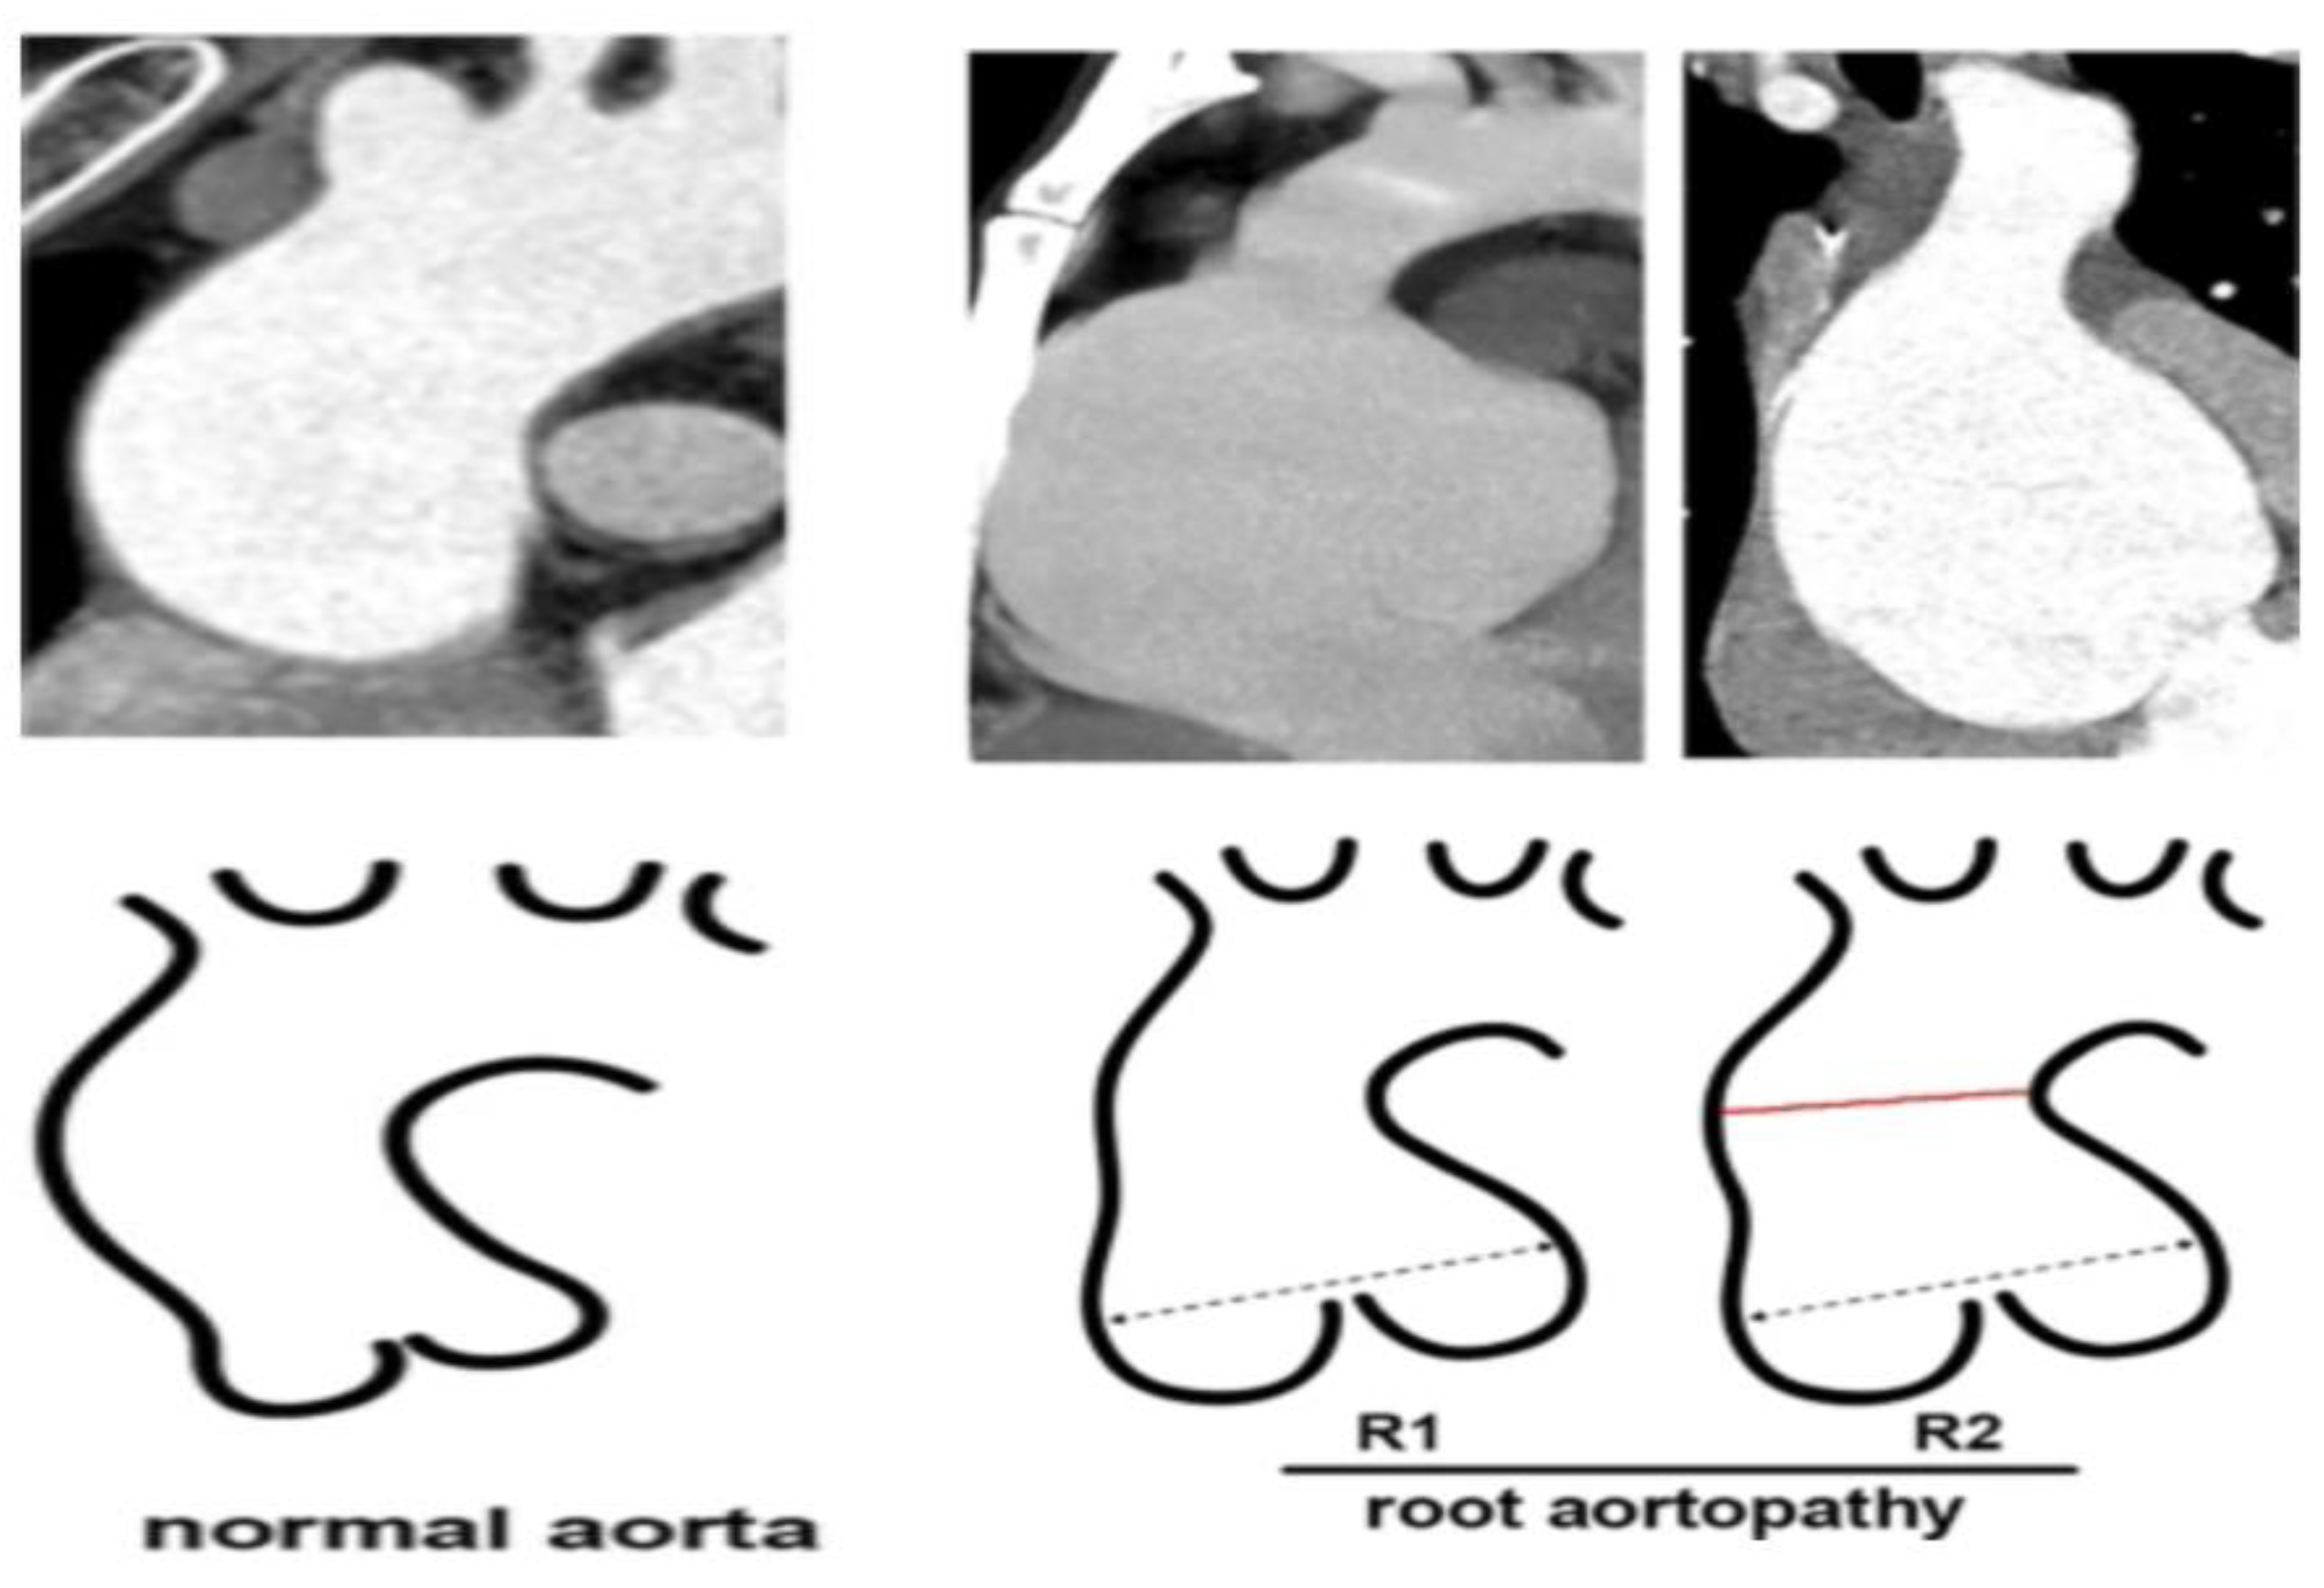

2.2.2. AR Associated with Aortopathy

- Ma, M.; Li, Z.; Mohamed, M.A.; Liu, L.; Wei, X. Aortic root aortopathy in bicuspid aortic valve associated with high genetic risk. BMC Cardiovasc. Disord. 2021, 21, 413. [Google Scholar] [CrossRef] [PubMed]

- Borger, M.A.; Fedak, P.W.; Stephens, E.H.; Gleason, T.G.; Girdauskas, E.; Ikonomidis, J.S.; Khoynezhad, A.; Siu, S.C.; Verma, S.; Hope, M.D.; et al. The American Association for Thoracic Surgery Consensus Guidelines on Bicuspid Aortic Valve–related aortopathy. J. Thorac. Cardiovasc. Surg. 2018, 156, e41–e74. [Google Scholar] [CrossRef] [PubMed]

- Sun, B.J.; Lee, S.; Jang, J.Y.; Kwon, O.; Bae, J.S.; Lee, J.H.; Kim, D.-H.; Jung, S.-H.; Song, J.-M.; Kang, D.-H.; et al. Performance of a simplified dichotomous phenotypic classification of bicuspid aortic valve to predict type of valvulopathy and combined aortopathy. J. Am. Soc. Echocardiogr. 2017, 30, 1152–1161. [Google Scholar] [CrossRef] [PubMed]